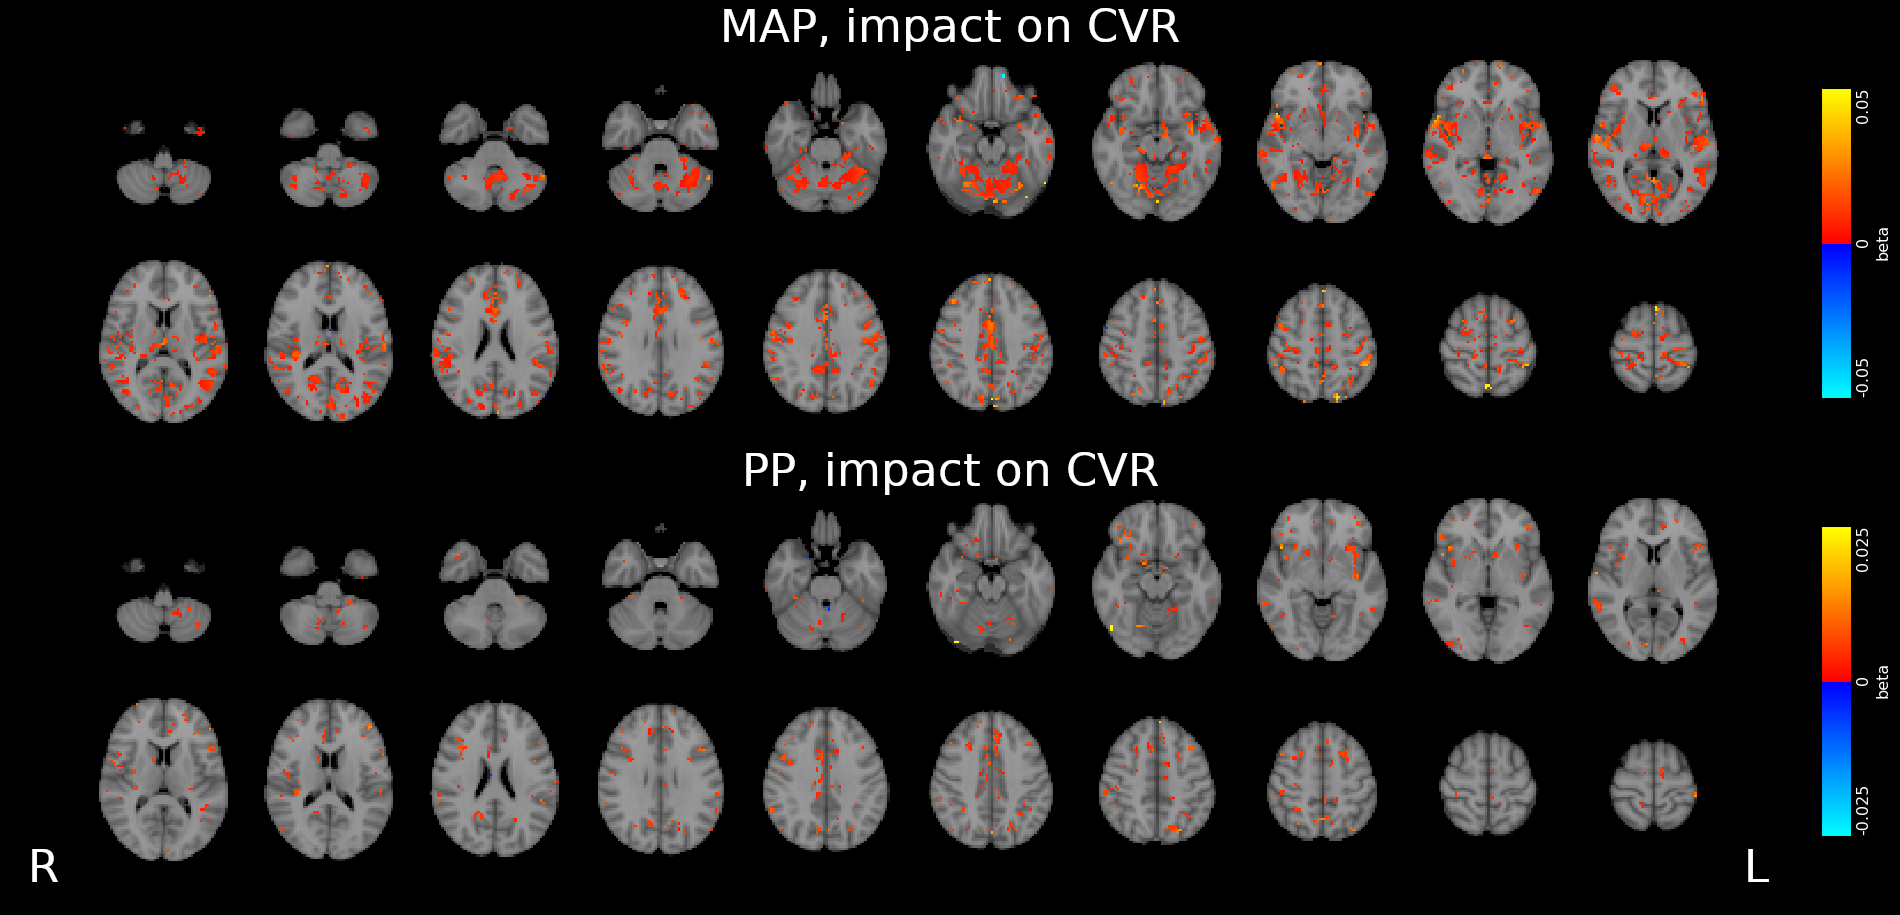

CVR and blood pressure

Due to its nature as homeostatic and cerebrovascular process, CVR is modulated by systemic changes in blood pressure¹

1. Fierstra et al. 2013 (J. Physiol.); 2. e.g. Hetzel et al. 1999 (Stroke)

Previous studies with Transcranial Doppler Ultrasound suggest to take into account blood pressure when measuring CVR²

To our knowledge, the impact of blood pressure on BOLD-fMRI based CVR estimation has not been assessed yet

We averaged the two measurements and computed the Mean Arterial Pressure (MAP) and the Pulse Pressure (PP):

Methods: effect of pressure

We used 3dLMEr¹ to set up the following LME models:

Results were thresholded at \(p<0.05\) after controlling for false discovery rate²

1. Chen et al. 2013 (Neuroimage); 2. Benjamini et al. 2006 (Biometrika)

*maps were smoothed 5mm FWHM

Methods: effect of pressure

We smooth CVR and lag maps using a dilated GM mask (white mask below) and a FWHM of 5mm (voxel size 2.5 isometric) before running 3dLMEr.

Results: blood pressure

Results: blood pressure

Results: blood pressure

Both MAP and PP should be taken into account in CVR experiments, especially in comparisons between subjects or between regions!

- Stationary blood pressure changes, expressed as MAP and PP, as well as sex, impact regional CVR estimation differently across sessions and subjects

-

Dynamic blood pressure changes are expected to impact CVR estimation, hence continuous blood pressure recordings are required to assess the matter